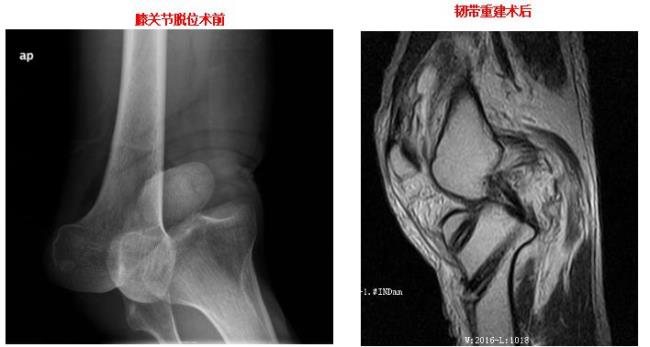

多发韧带损伤修复